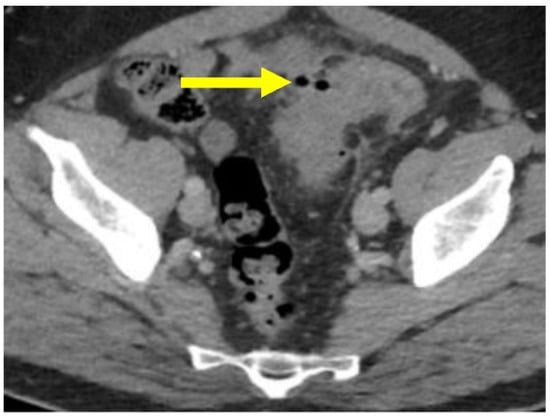

Diverticular disease is characterized by sac-like protrusions of the colonic wall. Left-sided colonic diverticula are more common in the West and are characterized by herniation of the mucosa through the muscularis propria at weak points in the wall where the vasa recti supply the mucosa and submucosa (Figure 1) [1,8,9]. Right-sided diverticula are generally true diverticula, more common in Asian countries, and herniate through all of the layers of the colon wall. For the purposes of this review, we will focus on left-sided “pseudo”-diverticula [4,10].

Figure 1.

Diverticulosis: Hematoxylin and eosin (H&E) stain shows the colonic mucosa (**) and submucosa (*) protruding through the muscularis propria in the sigmoid colon (H&E, ×15).

Asymptomatic diverticulosis is characterized by silent diverticula. It is frequently an incidental finding in patients undergoing imaging or endoscopy for other indications [1]. Histologically, asymptomatic diverticulosis shows non-inflamed colonic mucosa and submucosa protruding through the muscularis propria into the adventitia (subserosa) of the bowel wall (Figure 1). About 25% of people with asymptomatic colonic diverticulosis will experience an episode of symptomatic diverticular disease, and up to 5% will have an episode of acute diverticulitis, with or without complications [20,21].